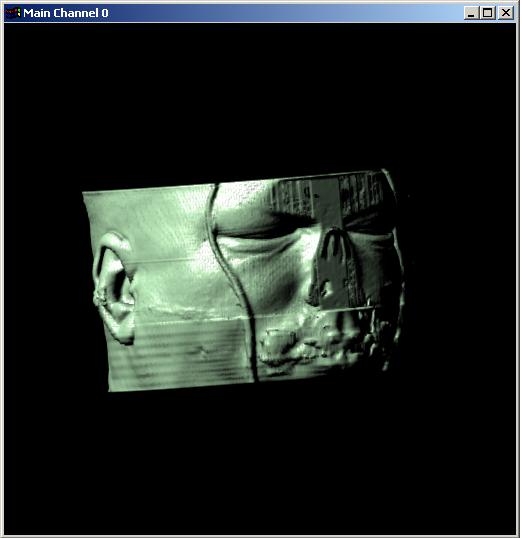

Visible human female CT data

Bone only

Data Resolution : 256x256x128

|

Visible human male CT data

Bone only

Data Resolution : 256x256x128

|

Visible human male CT data

Bone only

Data Resolution : 256x256x128

|

The following 12

images was generated by PC which has NVIDIA's GeForce3 GPU graphics card. The

hardware accelerated rendering techniques are used to make the following images.

To use the GeForce3 hardware, we have to use the OpenGL extensions like

GL_NV_texture_shader2, GL_NV_register_combiners, GL_EXT_texture3D,

GL_EXT_paletted_texture, GL_ARB_multitexture and so on. Since the GeForce3 card

allows the 3D texture shading, the image quality is better than the pixel of

frame buffer based shading in showing two materials at the same time.